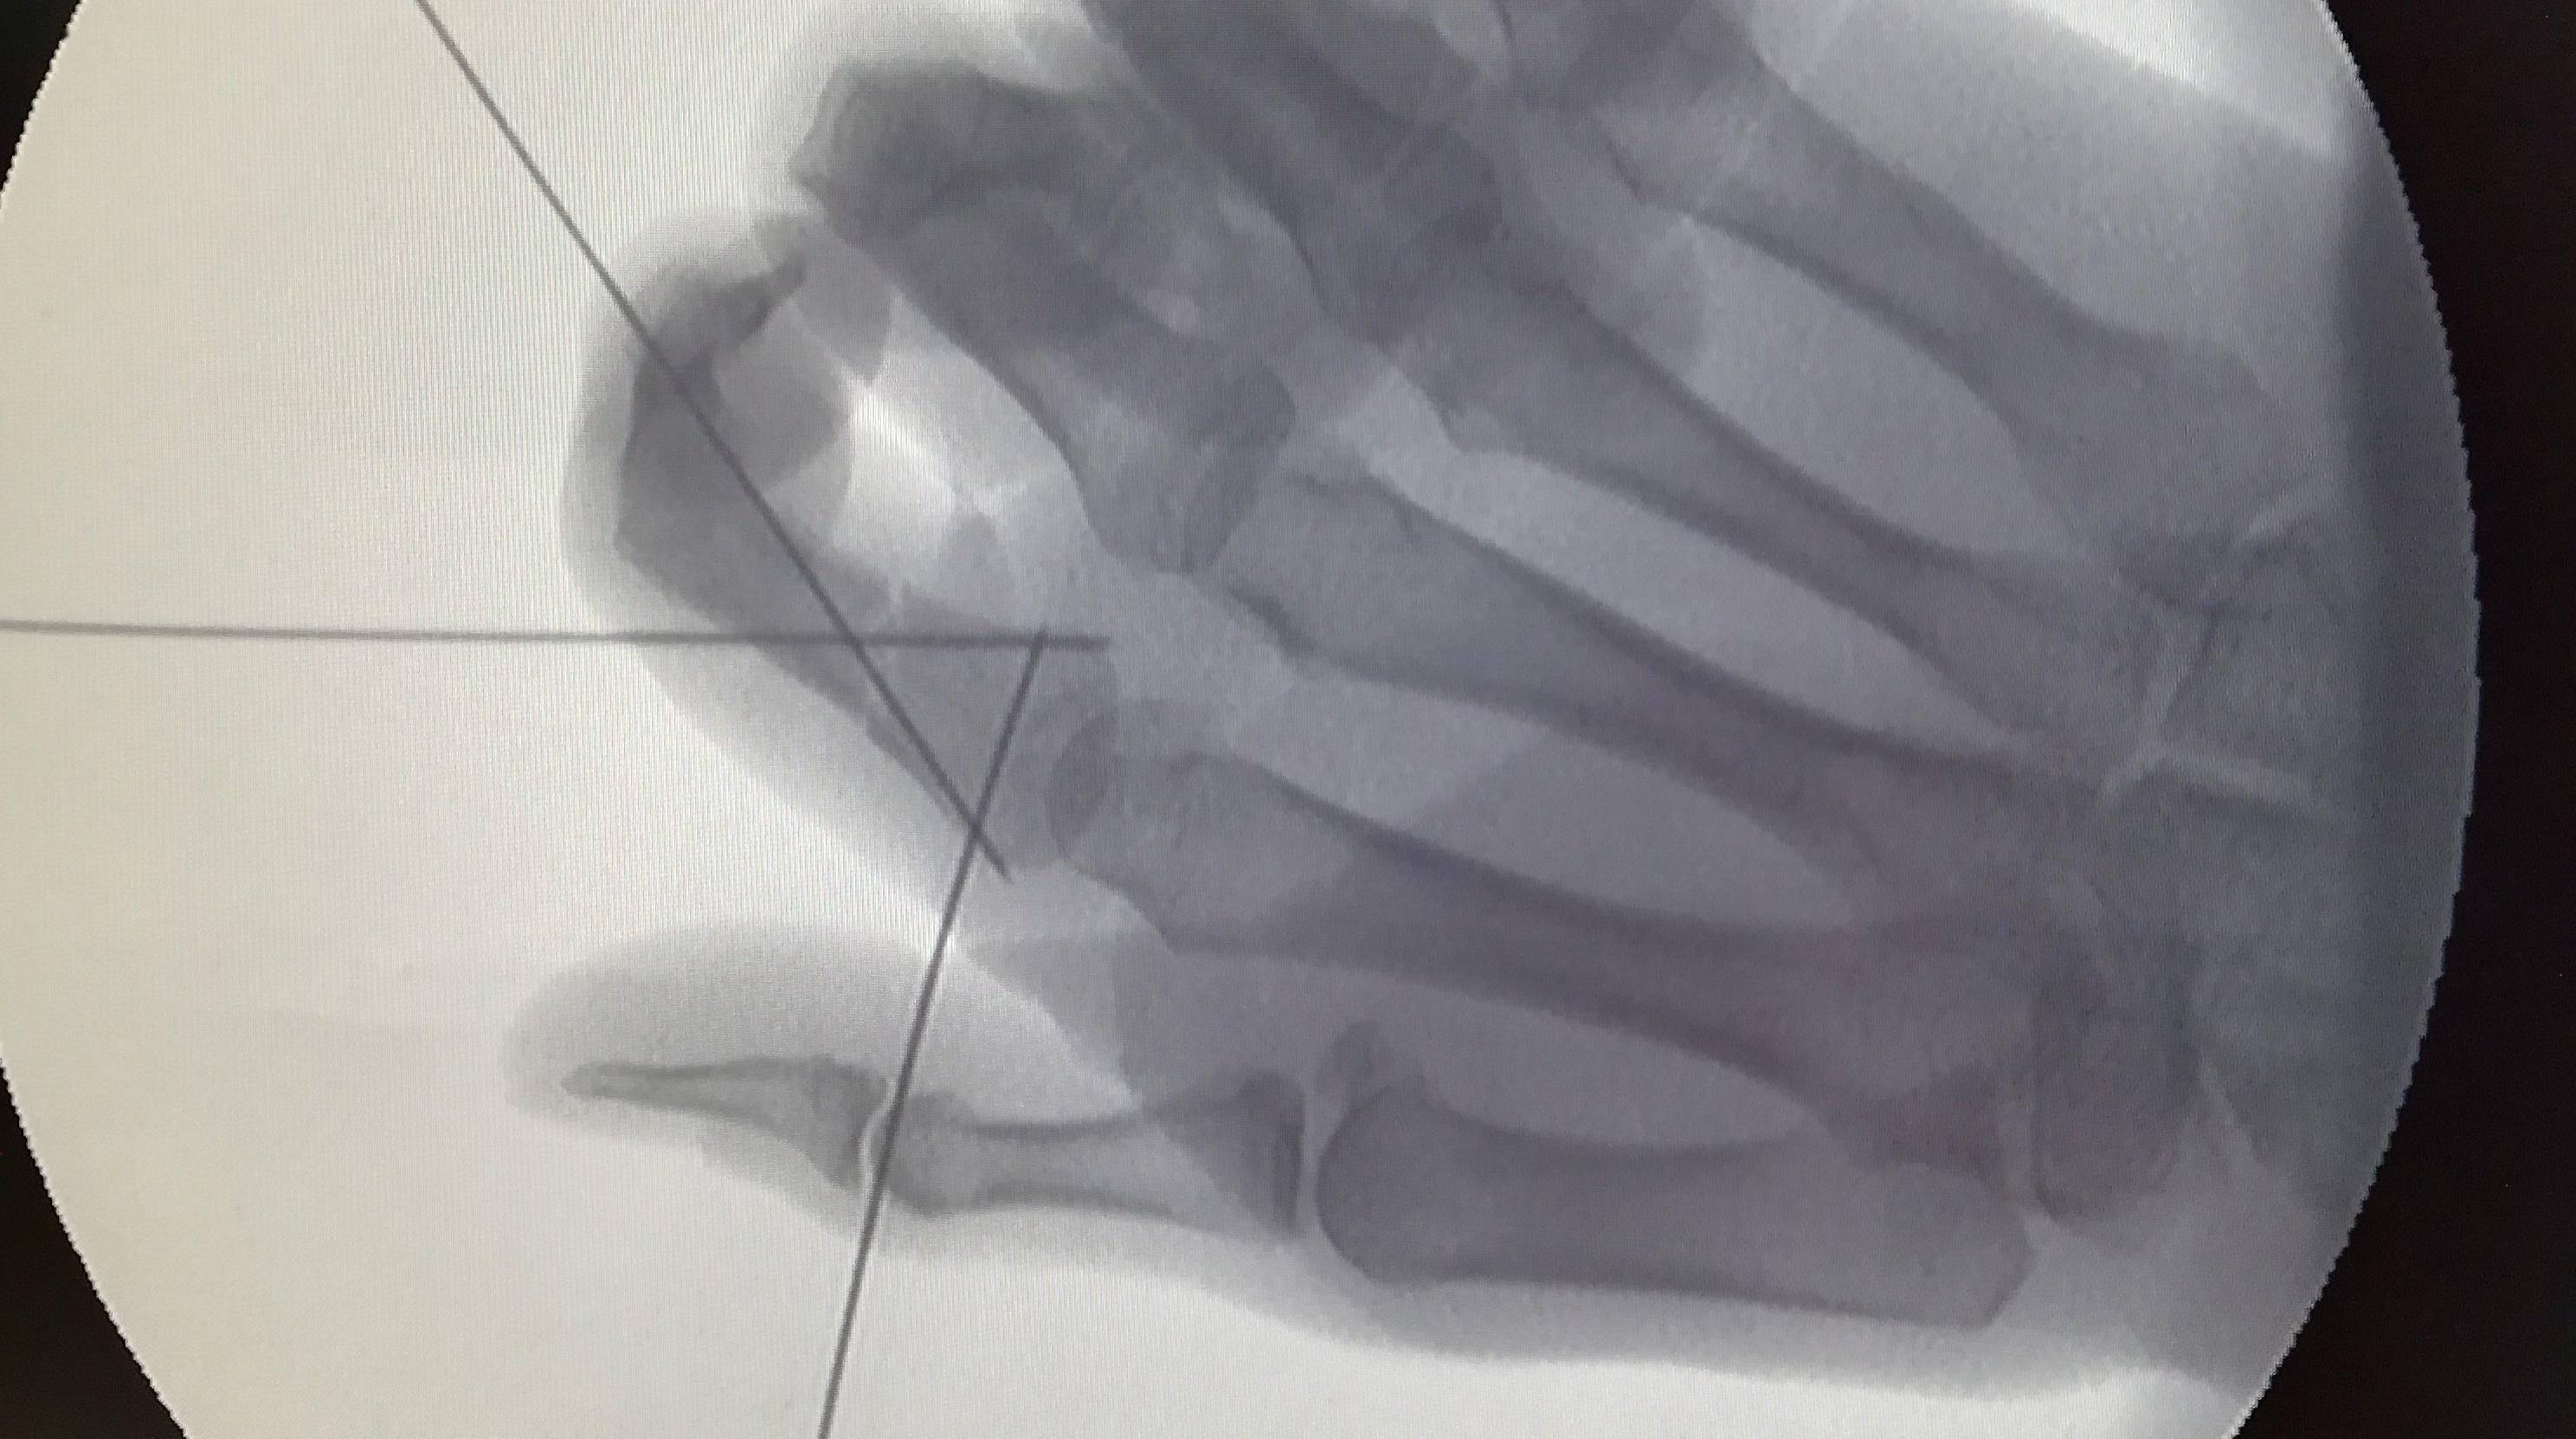

根据公开测试,为了让车门正常关闭,电吸机构需要向车门施加至少 600 牛的外力,才能在很短的路径中,实现关闭动作。如果不幸被夹住,约等于要让手指承担一个成年人穿着铁鞋单脚站立的力。

这样的力度,就算是变种人金刚狼来了,后果也是轻则乌青,重则骨折,更别提肉体凡胎的普通人了。

汽车媒体人韩路曾做过路特斯电吸门的夹断性试验,三个试验对象:剥皮火腿肠、带皮火腿肠和鸡爪,在遭受电吸门的挤压后,无一幸免,全部断折。

不少网友分享了自己遭遇电吸门”伏击“的经历:整个指甲被夹成瘀血紫色,慢慢脱落,然后再长新的,耗时五个月。